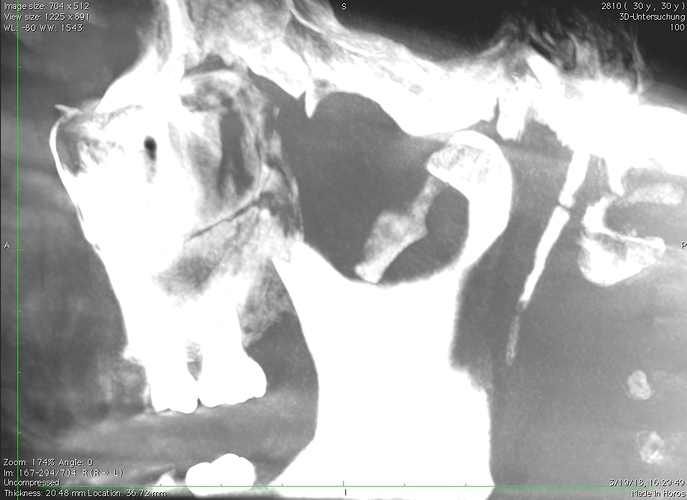

Have been trying to figure out for about 4 years now what the problem of my discomfort is. Since i’m starting to think doctors don’t really take me seriously anymore i started researching myself. some eagle syndrome seem very familiar but since it’s rather rare i really doubted it might be that. Many doctors appointments later still no clue. doctor suggested i might be grinding my teeth (which i doubt) and prescribed me physical therapy to loosen the muscles but it did not really help. A doctor made a 3d scan from my right jaw to check out some teeth and said everything is normal. now i started looking at the pictures myself and remembering this condition i started wondering if that styloid size can be considered normal.

So here’s the usual caveat…I am not a doctor so my opinion cannot be taken as a medical truth, but the fact that you have a gap at the end of your styloid & then what appears to be a second piece, says to me that either your styloid is broken or your stylohyoid ligament is partially calcified. In either case, the symptoms you’re suffering could absolutely be caused by the styloid process.

I second all that! The second piece of the styloid looks slightly lighter too, which could be that it’s not as dense in calcium, so could be a calcified ligament rather than a bone. It looks long to me, if you work out where even the first piece would be level with your jaw & teeth, it would be around your tonsil area I’d guess, & the ‘average’ length styloid isn’t that long. As Isaiah says though, we’re not doctors…

FANTASTIC!! So glad you got a proper diagnosis & have found a doctor to do your surgery. The CT scans you just posted clearly show your styloid is elongated w/ possible ligament calcification. Surgery should make a world of difference for you!